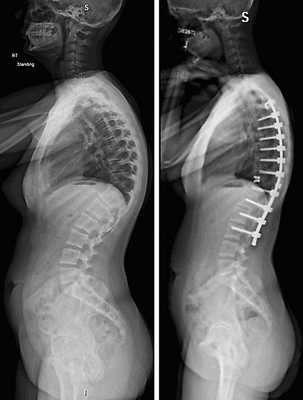

Коррекция кифоза грудного отдела.

- тяжелый сколиоз или кифоз;

- тяжелый кифоз, сколиоз 3-4 степени;